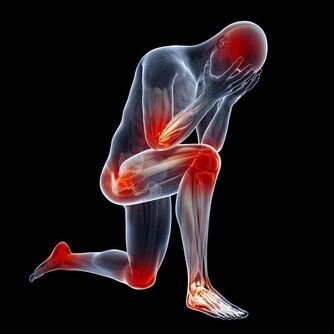

頸椎問題帶來4種健康狀況

頭暈、頭痛

70%的頭疼跟頸部有關,比如單側或雙側枕部、耳後悶脹或酸痛,

可伴有噁心嘔吐、耳鳴、眼脹,嗅覺或味覺改變。

頸椎病引起椎動脈供血不足,也會導致頸性眩暈。

胸悶

頸椎骨質增生、錯位失穩、椎間盤突出等會導致頸胸綜合徵,使人出現陣發性胸悶、心前區疼痛、窒息感。